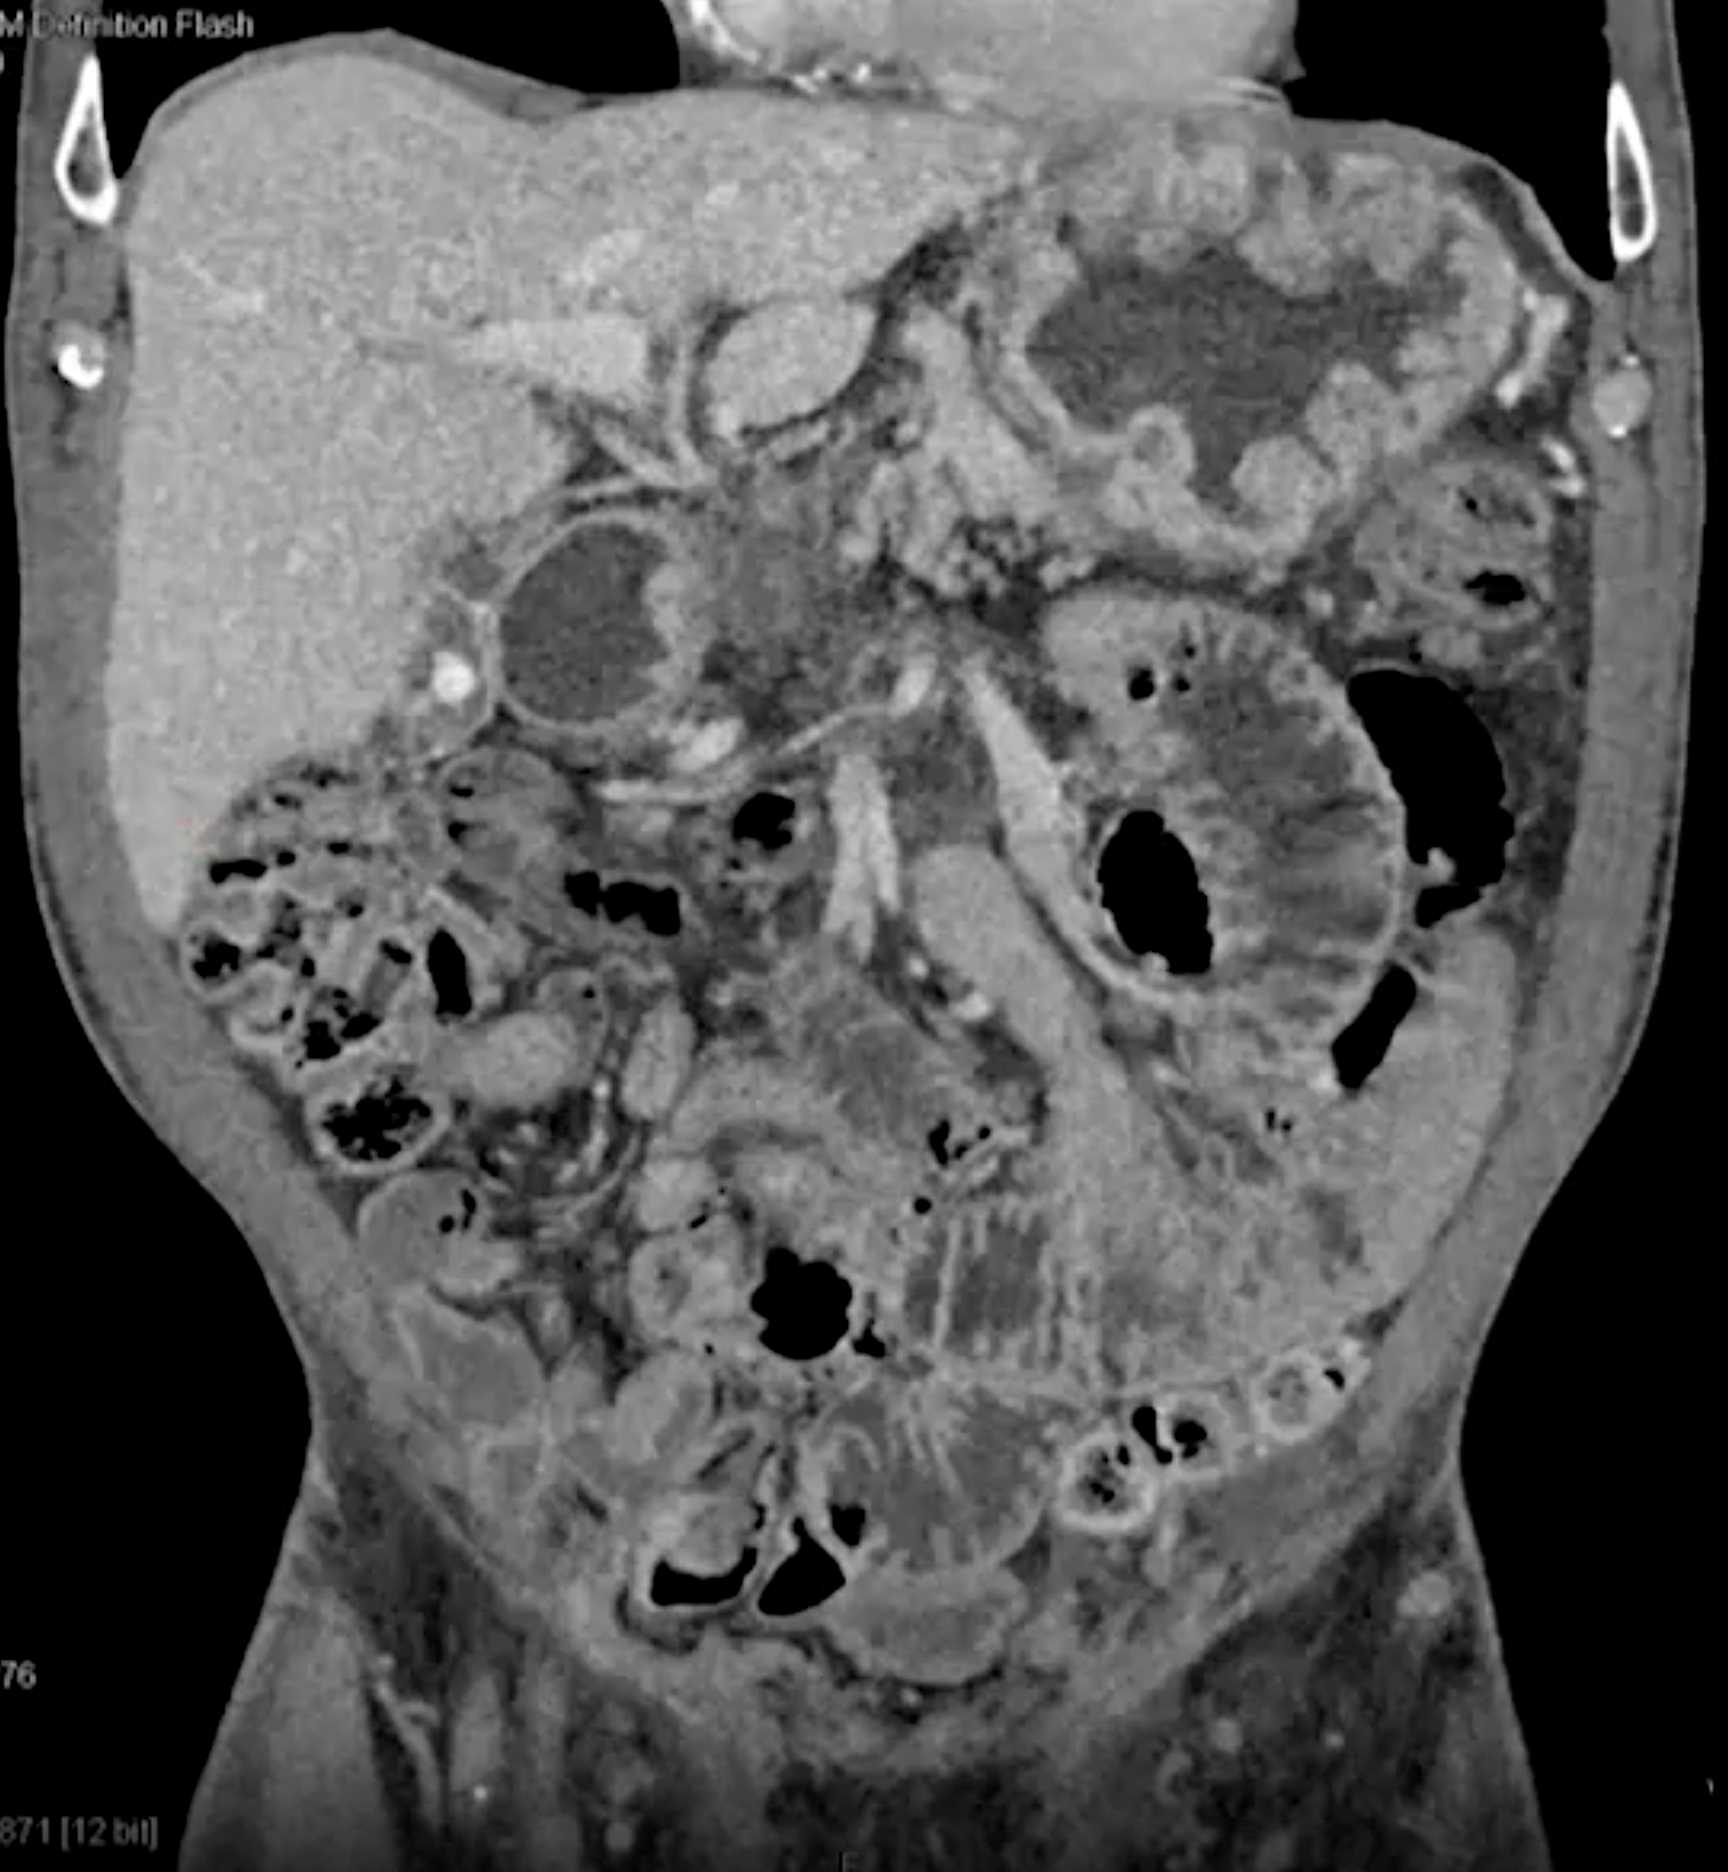

Chemical Gastritis due to NSAIDs